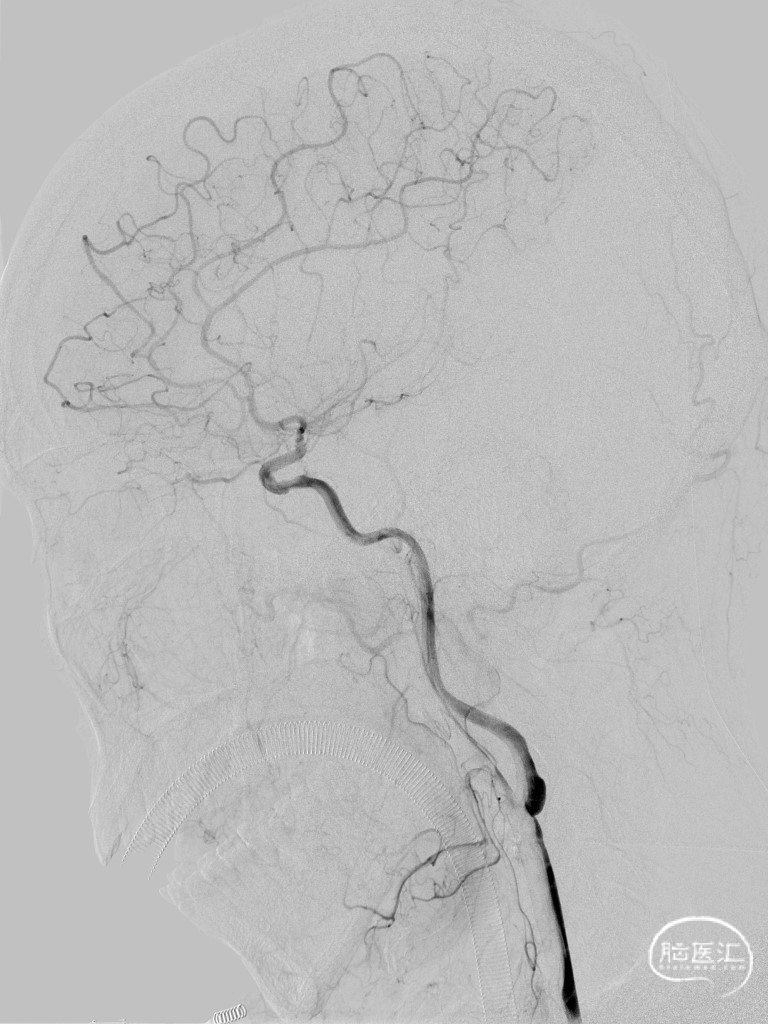

➢ 脑血管造影

➢ 术后造影